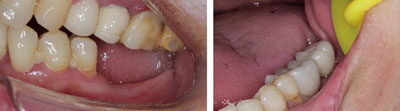

对于牙齿完全缺失的情况,我们还是建议做种植牙修复,种植牙有以下的优点:

1.它的咀嚼功能优于许多传统假牙。

2.具有较强的固位力与稳定性,可像真牙一样扎根在患者的口腔里。

3.可少磨或不磨自己的真牙。

4.不需要活动假牙必备的基托与卡环,没有大面积塑料基托导致的味觉迟钝与不舒适感。

5.体积小、不露金属、美观,有利于保持口腔清洁卫生。